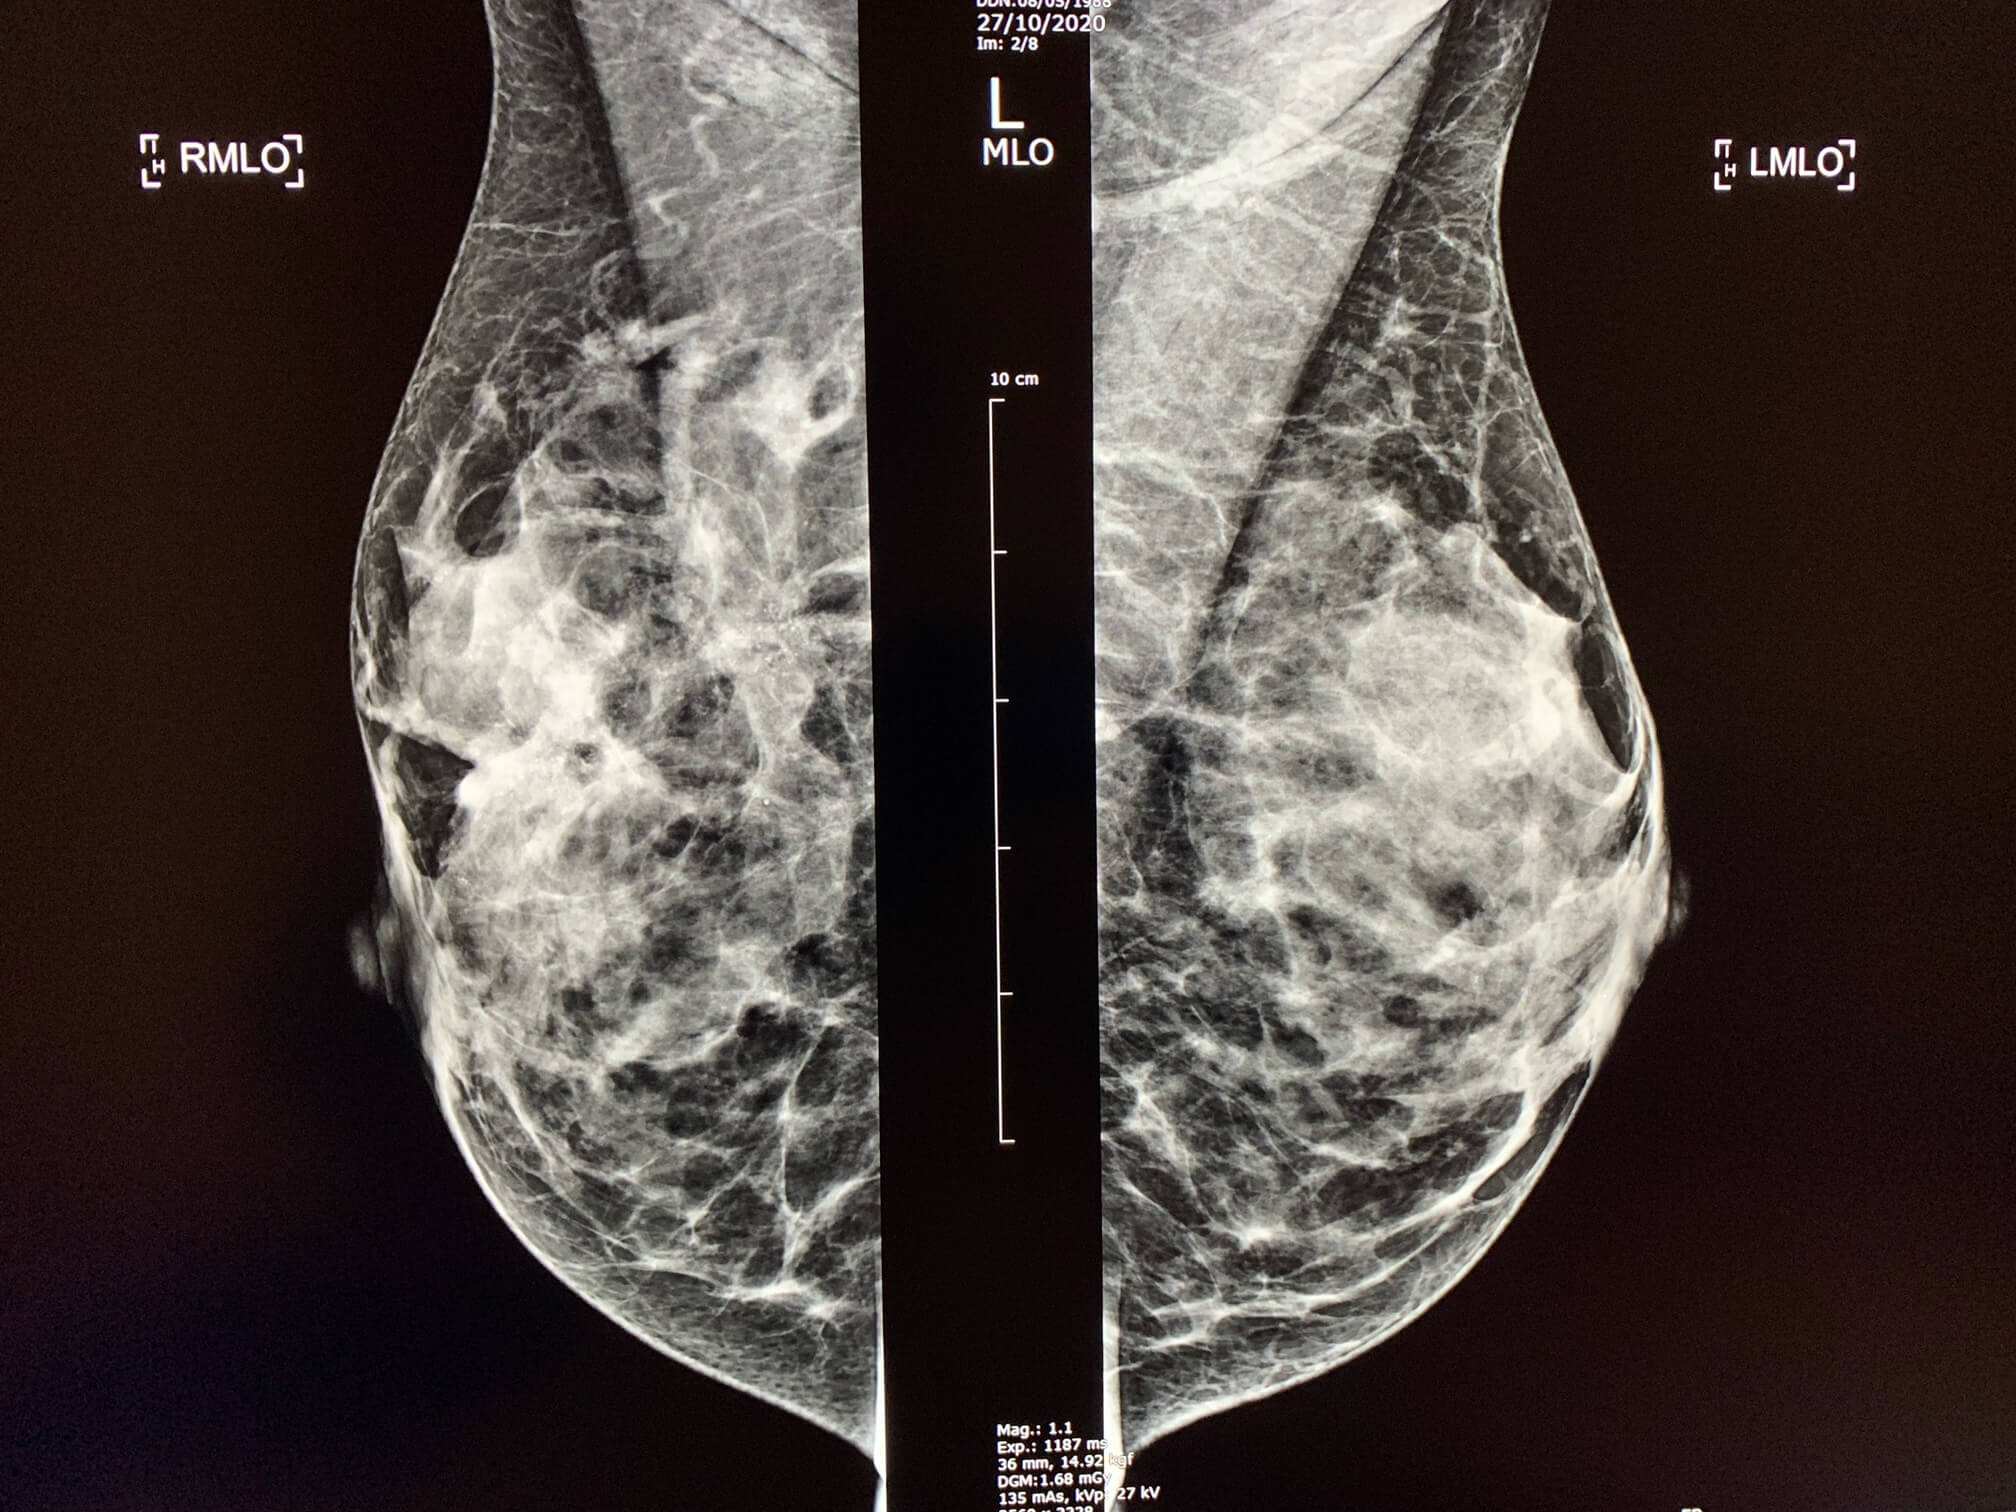

Case of the week (week 29, 2021)

MammoScreen® two suspicious lesions found

Woman with right breast swelling.

MammoScreen™ points to two suspicious lesions at mammography. These 2 lesions are found on the ultrasound as well.

Biopsy confirms luminal carcinoma (RH+, HER2-).